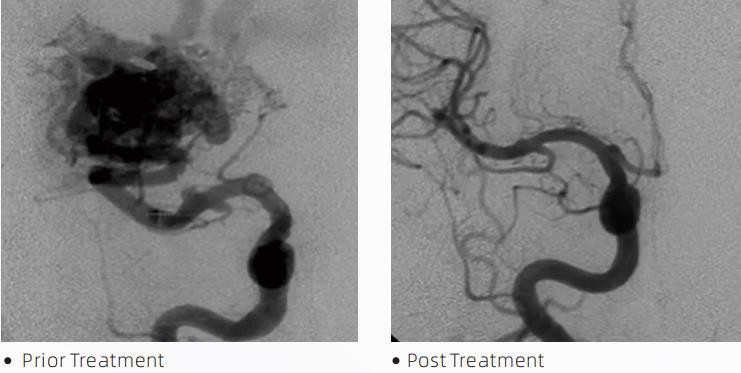

LaavaTMLiquid Embolic System on sekkuv endovaskulaarne ravi tserebrovaskulaarsete väärarengute raviks. Tserebrovaskulaarne väärareng viitab hea- või pahaloomuliste neurovaskulaarsete kõrvalekallete rühmale, mis võib põhjustada intrakraniaalset hemorraagiat, ajuinfarkti, ajuisheemiat ja muid haigusi. Vedel emboliseerimissüsteem on lihtsa intravaskulaarse sisestamise teel manustatav meditsiiniseade, mis emboliseerib ebanormaalseid ajuveresooni spetsiaalse vedela materjali süstimise teel. Vedel materjal moodustab veresoontes kontrollitud koeemboolia, mis võib vähendada tserebrovaskulaarsete väärarengute mõju patsientidele. Emboliseerimiskohale juurdepääsuks kasutatakse DMSO-ga ühilduvat manustamismikrokateetrit, mis on näidustatud kasutamiseks neurovaskulaarsüsteemis. Laava vedel emboolia on mittekleepuv vedel emboolia süsteem, mis koosneb EVOH (etüleenvinüülalkohol) kopolümeerist, mis on lahustatud DMSO-s (dimetüülsulfoksiid) ja suspendeeritud mikroniseeritud tantaalipulbrist, et luua fluoroskoopiaga visualiseerimiseks kontrast. LaavaTMon saadaval kolmes tootekoostises: LAVA-12, LAVA-18 ja LAVA-34. LAVA-12: soovitatav distaalsete mikroveresoonte toitmisel ja väikeste söötjate kaudu. LAVA-18: soovitatav, kui söötmisel tehakse pedikle süstimine niduse lähedale; LAVA-34: soovitatav suurema voolavuse ja suuremate fistulaarsete komponentide emboliseerimiseks.